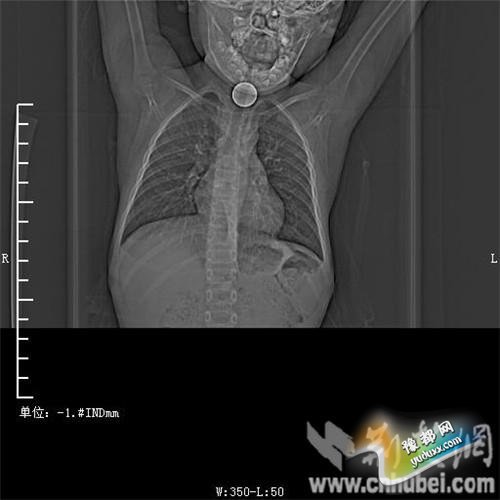

图为:硬币卡在了阳阳的喉部 图为:硬币卡在了阳阳的喉部

消化内主任方向明告诉记者,孩子送来时已经是晚上8点15分,医护人员立即给孩子拍胸部CT确定硬币的位置,8点30分,方向明通过胃镜下食管异物取出术,成功的将这枚一元硬币取了出来。1月5日上午,阳阳顺利出院,医生护士在他出院时不断告诉他,以后千万不要吞含异物。